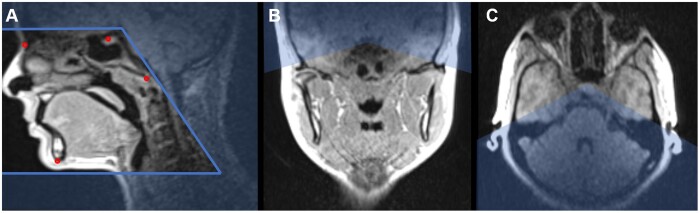

O equipamento funciona de maneira semelhante a uma ressonância hospitalar, mas com adaptações importantes. O paciente fica deitado e uma antena específica capta imagens da região maxilofacial, incluindo boca, mandíbula, maxila e seios maxilares.

“Ela lembra uma ressonância tradicional, mas é menor, mais leve e focada apenas na região da face. Isso torna o exame menos claustrofóbico e mais confortável para o paciente”, diz o pesquisador.

2- Foco em Tecidos Moles: O equipamento é otimizado para gerar imagens detalhadas de tecidos moles na região bucal, algo difícil de visualizar com métodos convencionais.